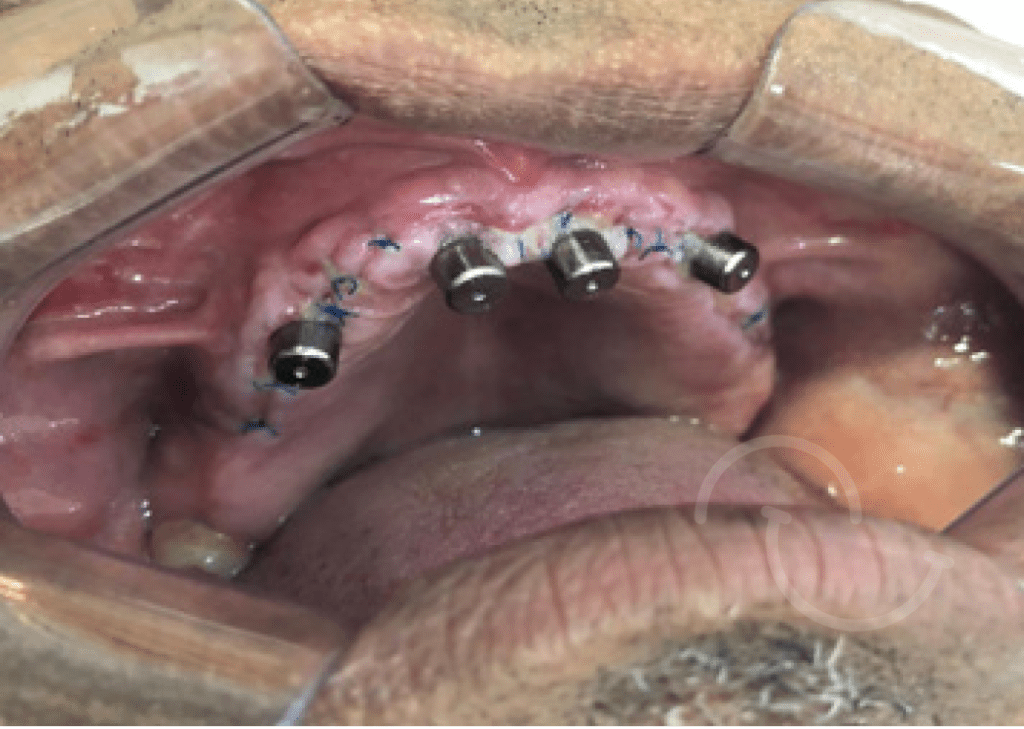

Casos clínicos de implantes dentales